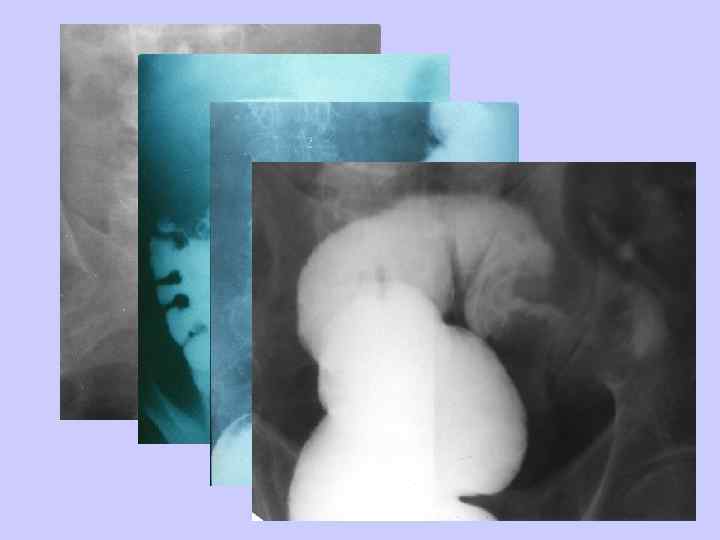

ДИАГНОСТИЧЕСКИЙ АЛГОРИТМ • • • Пальцевое исследование прямой кишки Ректосигмоидоскопия Ирригоскопия Колоноскопия Гистологическое исследование